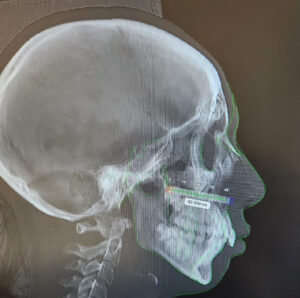

3D Printing in Healthcare has transformed the way industries like healthcare, automotive, manufacturing, and design operate. 3-D labs have revolutionised...

IntroductionCorrective jaw surgery, also known as Orthognathic surgery, changes the structure of your jawbone and brings your upper and lower...